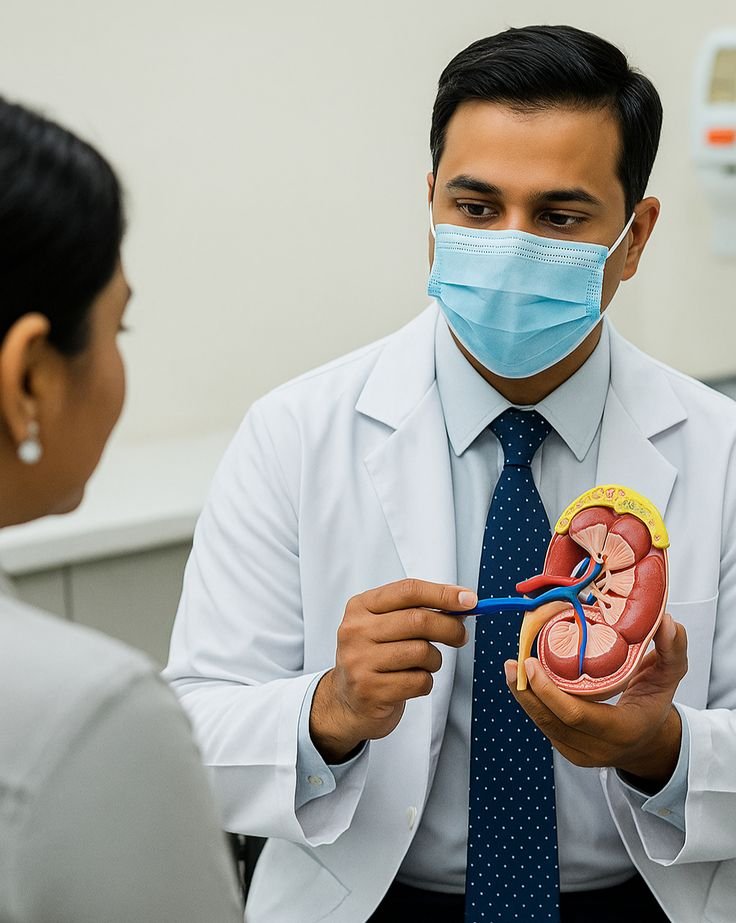

Urology

Advanced urology services treating kidney stones, prostate disorders, urinary infections and male health conditions with precision care.